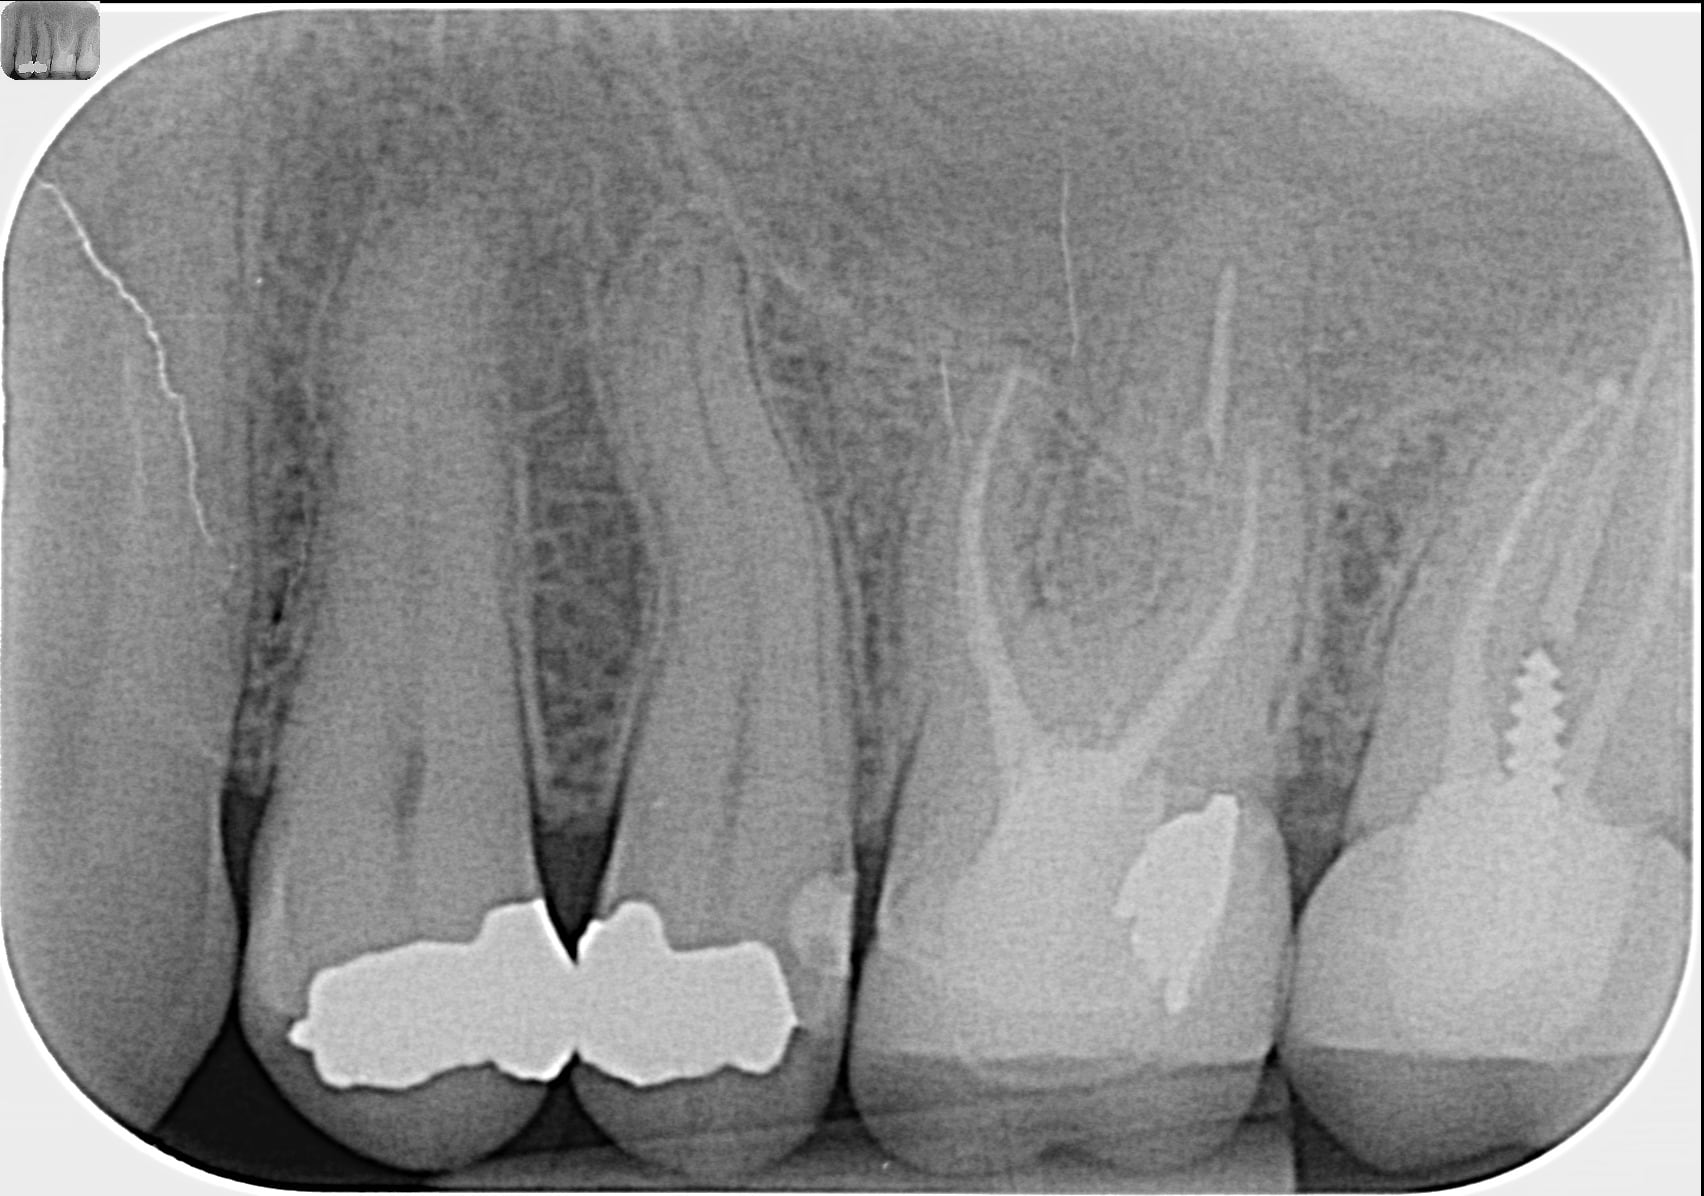

En PJ la rétro de la zone prise en 2016, 2018 et il y a un mois

elle dit : " PJ la rétro de la zone prise en 2016, 2018 et il y a un mois "

tu y vois une perte d os en 3 ans , toi ? moi non .

La couronne de 37 a un profil d'émergence mésial en surcontour

On pourrait comparer si la taille de la chambre pulpaire est diminuée sur 36 par rapport à 46. Signe d’une « souffrance » de type occlusale ou fêlure...

L expression paro existe entre la 6 et la 7 l os cortical disparait au sommet du septum.

A mon avis c est occluso chez une bruxomane nocturne + syndrome du septum (radio + douleur aliment filandreux)